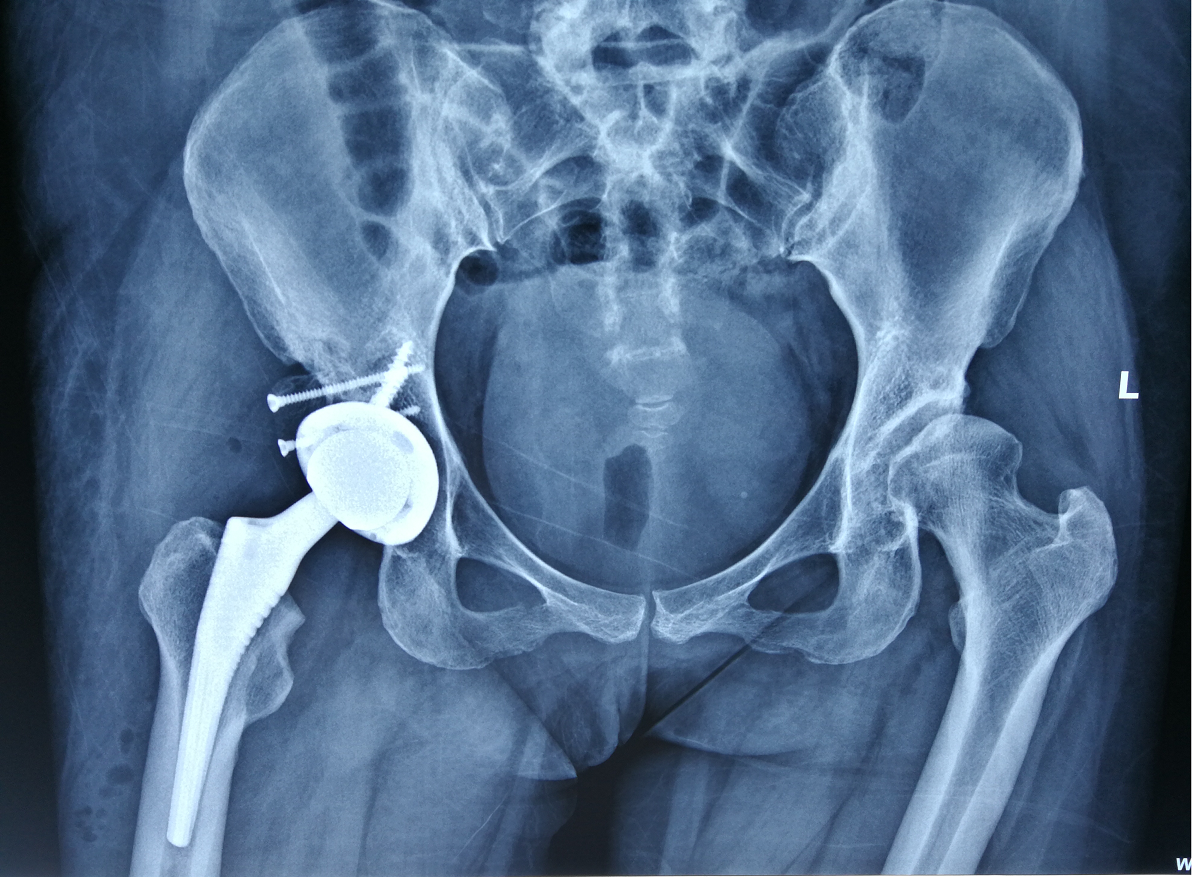

术中打磨好髋臼,安放完髋臼杯以后发现臼杯上方骨覆盖明显不足,于是利用截掉的股骨头做出大小合适的植骨块,将植骨块打磨、雕刻成与髋臼相匹配的形状,并把植骨块使用螺钉固定在无骨质覆盖的髋臼上方。

术后复查髋关节正位片显示,右侧髋关节置换术后,假体位置满意,植骨块位置合适。